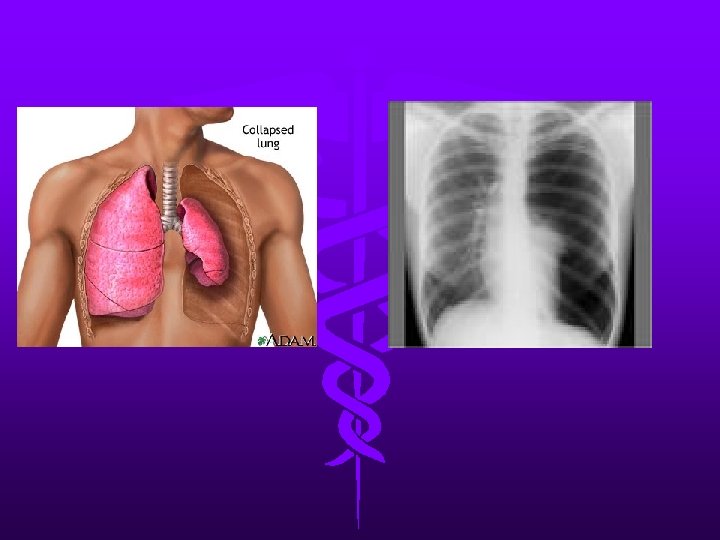

Pneumothorax • Accumulation of air between parietal and visceral pleura • Results in severe V/Q mismatch and hypoxia • S/S: –chest wall hyperresonant to percussion –Breath sounds decreased or absent unilaterally –Subcutaneous emphysema –CXR confirms